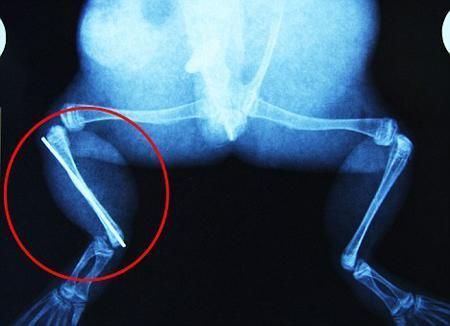

環(huán)球網(wǎng)4月2日?qǐng)?bào)道 據(jù)《每日郵報(bào)》報(bào)道,上個(gè)月,南非大牛蛙布魯萊的右小腿被鄰居家的一只狗咬到,導(dǎo)致粉碎性骨折,現(xiàn)在經(jīng)過2個(gè)小時(shí)的手術(shù),它的斷腿已經(jīng)被接上,它也因此成為有史以來第一只通過外科手術(shù)用鋼針接上斷腿的青蛙。

布魯萊的主人,居住在南非約翰內(nèi)斯堡附近的62歲的安妮·米恩斯說:“我對(duì)這只青蛙如此關(guān)心,人們一定認(rèn)為我瘋了,但是我無法眼睜睜看著它那么痛苦。青蛙因其靈活的腿腳而著稱,一想到布魯萊的腿里要留下一個(gè)薄金屬片,我就感到心痛。然而我知道,如果不進(jìn)行手術(shù),布魯萊以后就沒辦法動(dòng)彈了。因此我匆匆趕到獸醫(yī)那里,央求他給這只可憐的青蛙動(dòng)手術(shù)。這位獸醫(yī)整天救助小貓小狗,他很難理解為什么我這么擔(dān)心一只青蛙,但是最終他還是答應(yīng)了給布魯萊做手術(shù)。手術(shù)后是幾個(gè)小時(shí)的焦急等待,我們希望它能快快蘇醒過來。不過現(xiàn)在它的傷口已經(jīng)愈合,又能在花園里跳來跳去了。X光照射顯示,它會(huì)恢復(fù)的跟以前一樣!

野生生物專家安妮經(jīng)常為學(xué)校寫教材,她認(rèn)為這是人類第一次通過手術(shù)給一只青蛙接斷腿。在手術(shù)開始階段,獸醫(yī)把少量給狗用的麻醉藥注入到這只青蛙體內(nèi),讓它失去知覺。然后他在布魯萊的斷腿上切開一個(gè)小口,把一根小鋼針植入腿里。最后獸醫(yī)給它縫了9針,把切口縫合在一起。僅僅幾周后,布魯萊就能在安妮家附近活動(dòng)了。這只青蛙大約已有25歲,主要以嚙齒動(dòng)物、蛇和其他青蛙為食。布魯萊所屬的牛蛙種群正在不斷減小,目前只能在非洲南部的濕地里才能看到這種青蛙。